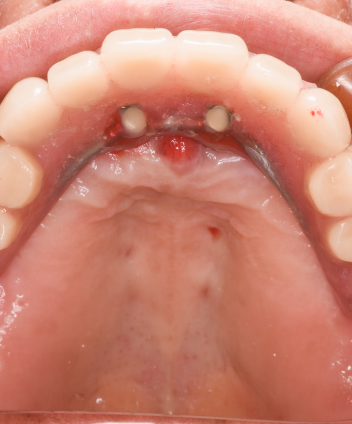

インプラント手術(4本埋入)+仮歯装着

STEP03

インプラント手術(4本埋入)

+仮歯装着Implant surgery

静脈内鎮静法を併用し、リラックスした状態で手術可能。当日中に仮歯を装着することで、見た目・機能をすぐに回復できます。